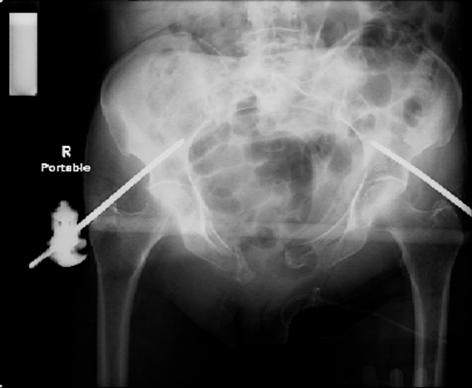

attached are images of a 70 year old female after peds versus car. her own car ran her over.

injuries are limited to the pelvis. left rami open and visible in a 10cm vertical laceration just lateral to left labia majora. wound is grossly clean. no vaginal and no urinary issues. CT scan shows widening of both SI joints anteriorly but I think this is vertically stable pattern.

pt treated that night with I/D and supra-acetabular frame to close the ring. consideration was given for SI screws bilateraly, but given time of night and other factors decision made not to proceed.

so the question is what next operatively if anything? concerns are infection, nonunion anteriorly and possible incompetence of the pelvic floor which may lead to prolapse issues. right rami are comminuted and plating may entail ilioinguinal approach to extend plate laterally to right iliac wing. retrograde screw up right rami is an option but I am not convinced it will add much. adding SI screws very doable, but major concern is restoring anterior ring. so far wound is clean and closed over a drain, and I have no plans to open it back up and wash again.

maintaining pelvic alignment in ex-fix in 70 yo female for any length of time may be challenging.

any thoughts? would anyone plate the pubic symphysis to close the gap and leave the more lateral rami fractures alone? the most recent pelvic case on this website involved pts with suprapubic catheters and antibiotic options including resorbable beads. I wonder how many people would plate and place antibiotic beads. thanks.

it is good to hear from you. this lady is an independent ambulator, lives alone, drives a pick-up truck (which ran her over), and she is healthy. GYN pelvic exam was completed pre-operatively and CT scan with contrast did not show any bladder/urethral leaks. no blood has ever been noted from foley catheter or from the vagina. pretty amazing given the diastasis.

in terms of stressing the pelvis intra-operatively to assess overall stability, the trauma AP pelvis and CT scan provided plenty of info. I suppose one could stress the vertical stability, but again to what end? this pt had nearly 8cm of diastasis. rotational instability was a given. in terms of a lateral pelvic xray, I cannot say that besides a false profile lateral for hip dysplasia, I am not aware of lateral pelvic xrays for pelvic ring disruptions. if this is something that you do I would be interested in seeing an xray or two.